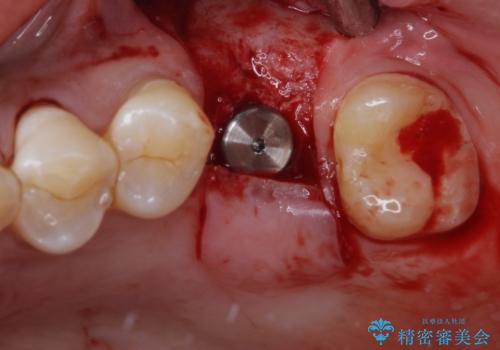

詰められた材料や壊死した組織を除去したところ、鮮明な破折線が認められたため、速やかに抜歯し、傷や骨の治癒を待って、サイナスリフトにより骨高さの低い部分にインプラント埋入を行いました。